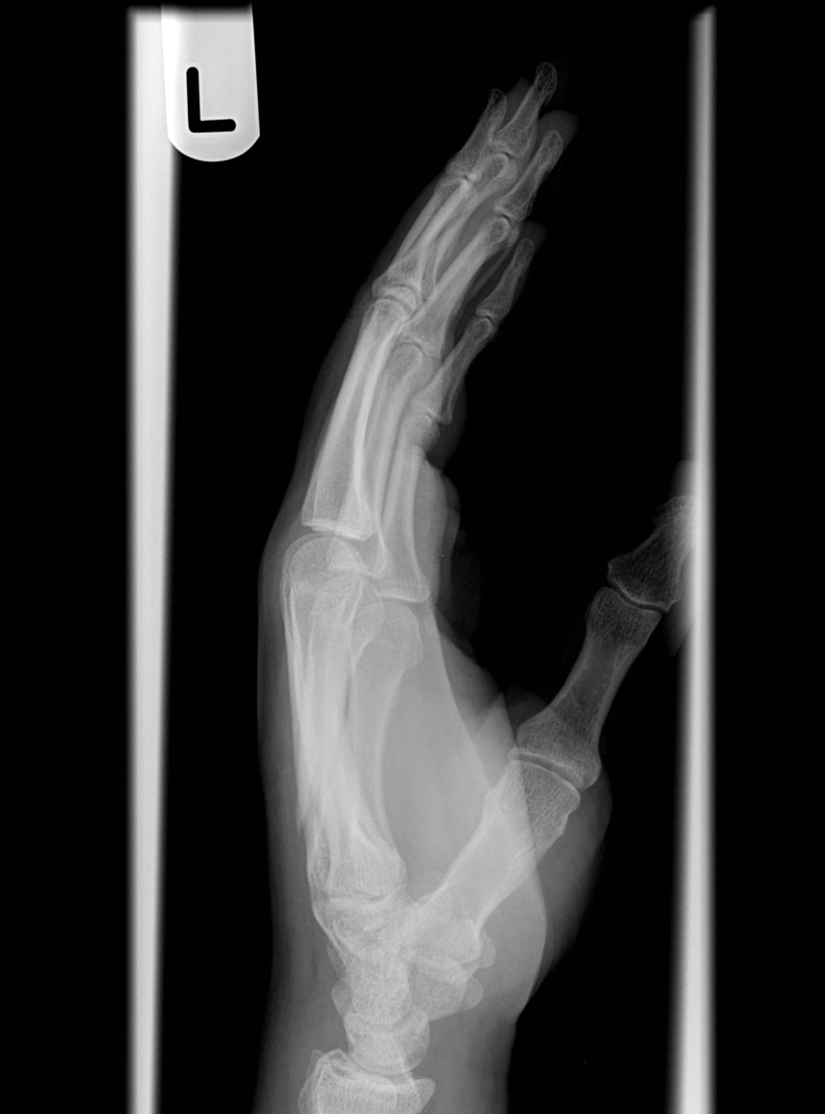

what view is this?

lateral wrist